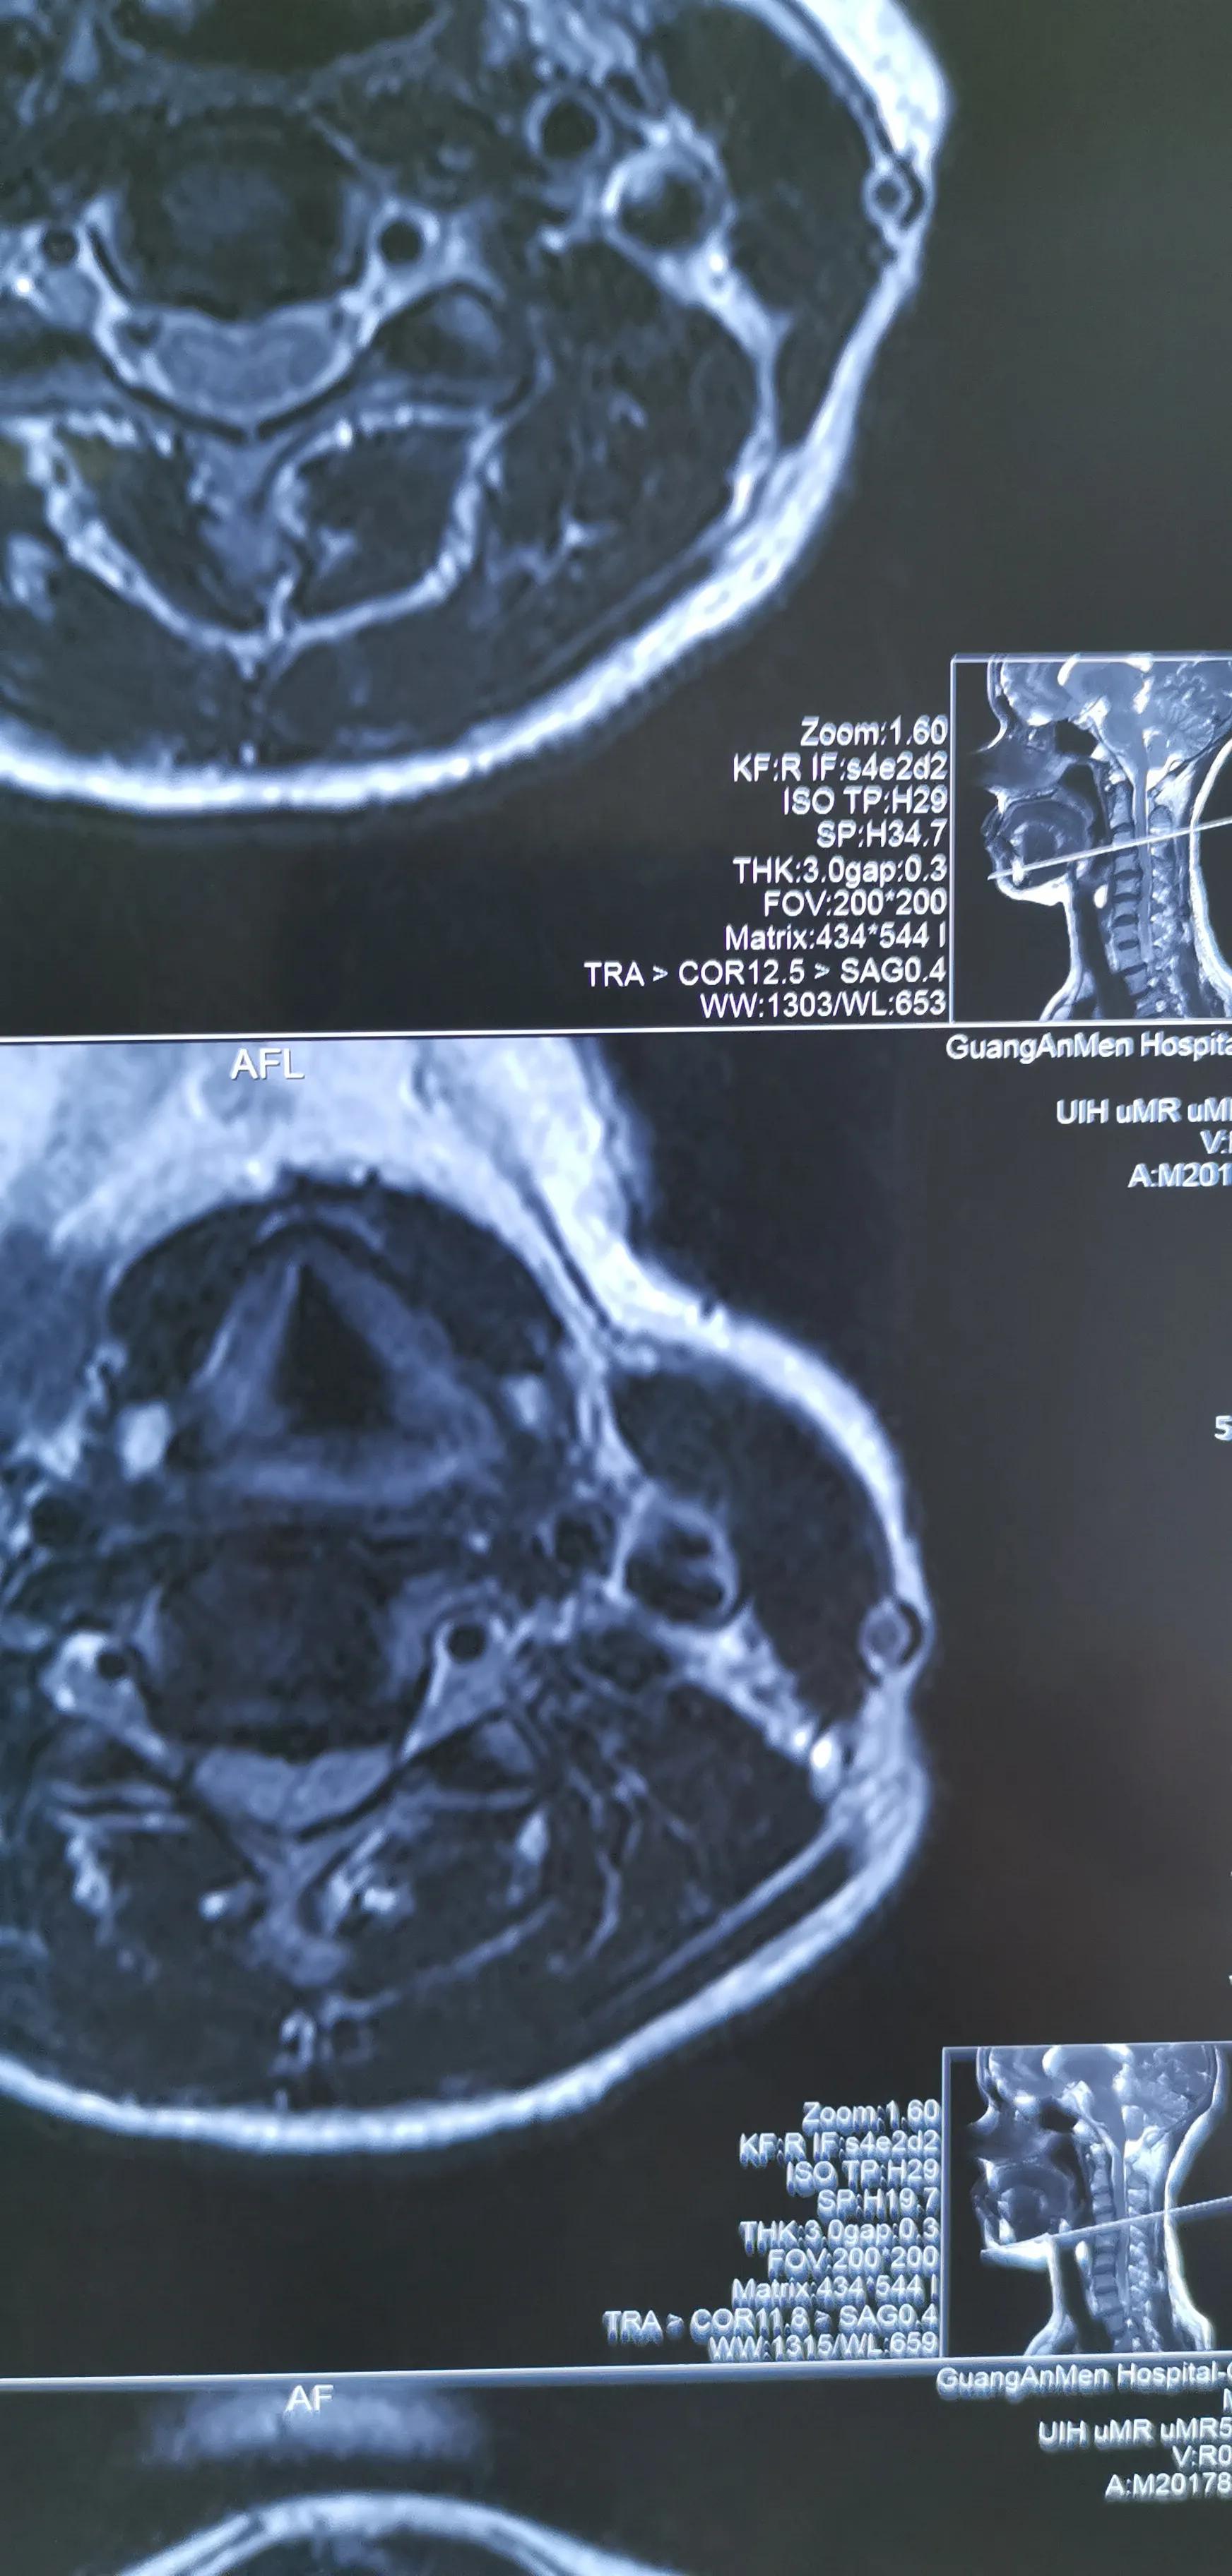

43岁女性,颈肩部疼痛严重伴左侧上肢放射痛无力,mri提示C4/5,C5/6椎间盘突出,CT提示钙化。予前路C5椎体次全切除,椎间盘摘除,椎间钛笼植骨融合钢板内固定,术后疼痛基本消失,肌力逐渐恢复,麻木缓解。

对这类椎间盘突出钙化的患者如果疼痛严重或伴肌力下降或行走不稳,提示压迫神经或脊髓,不宜推拿,可手术减压,效果显著。